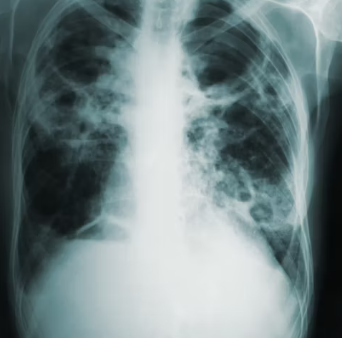

천식 진단에 있어 가장 핵심적인 검사는 폐기능 검사(Spirometry)입니다. 폐기능 검사를 통해 기관지 협착 유무를 확인하고, 특히 기관지확장제 흡입 후 반응(가역성)을 평가하여 천식을 진단합니다. 청소년 및 성인 천식 진단 시, 기관지 확장제 투여 후 FEV1(1초간 강제 날숨량)이 12% 이상, 그리고 200mL 이상 증가하면 가역성을 확인하여 천식을 진단할 수 있습니다.

이 외에 메타콜린 기관지 유발 검사로 기관지 과민성을 확인하며, 알레르기 피부 반응 검사나 혈액 검사(특이 IgE 항체)를 통해 알레르겐을 파악하기도 합니다. 의료진은 이러한 검사 결과를 종합하여 천식의 진단과 중증도를 판단합니다.

의료진은 임상 증상, 폐기능 검사 결과, 그리고 기관지확장제 반응을 종합하여 천식을 진단합니다. 이때 만성폐쇄성 폐질환(COPD), 기관지 확장증, 만성 기관지염, 위식도 역류 질환 등 유사한 호흡기 증상을 유발하는 다른 질환들과의 정확한 감별 진단을 내리는 것이 매우 중요합니다.